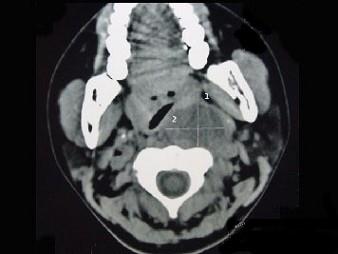

问题 女性,34岁,自诉1个月前被咽喉部被鱼刺刺伤,近半个月发热,咽喉部疼痛,CT检查如图所示,请选择正确的描述和结论 ( )

选项 A、考虑神经源性肿瘤 B、考虑血管瘤 C、肿块内密度均匀 D、考虑咽后壁脓肿 E、左侧咽后壁可见低密度肿块影

答案 CDE